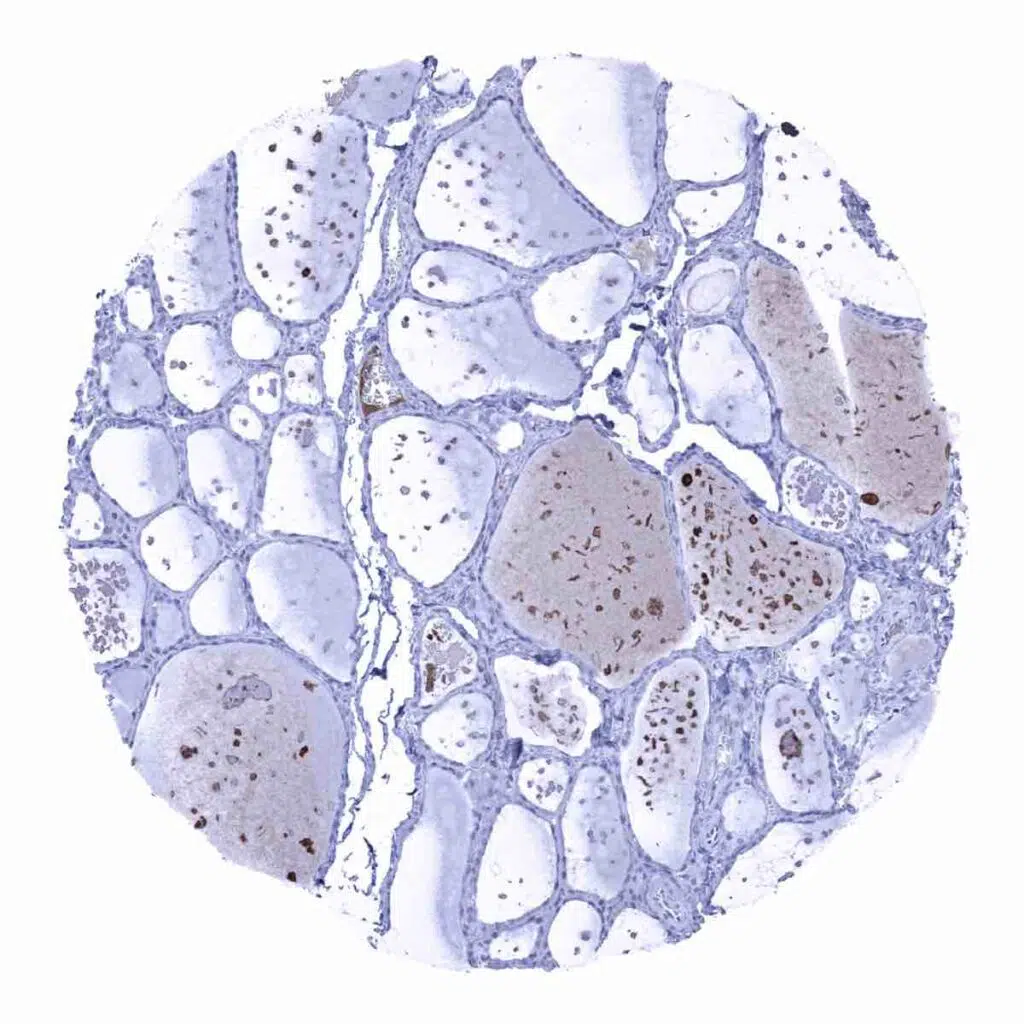

Thyroid gland – Some Rabbit anti-human IgA staining can occurs in the colloid of some follicles